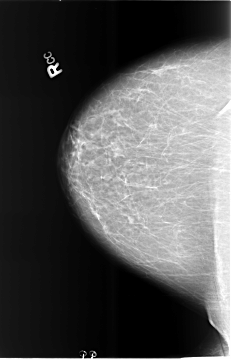

B_3473_1.RIGHT_CC

RIGHT_CC LINES 5736 PIXELS_PER_LINE 3688 BITS_PER_PIXEL 12 RESOLUTION 50 NON_OVERLAY